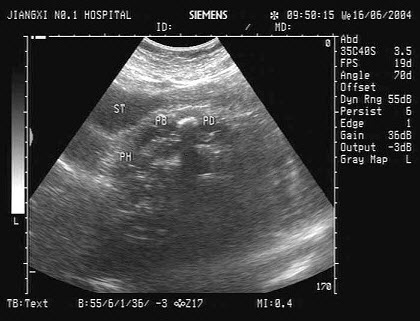

53、单项选择题

根据超声声像图,提示结构为()